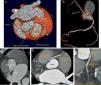

Case reportA 56‐year‐old woman, with a history of hypertension, hypothyroidism and anxiety attacks, was seen in the emergency department for constricting chest pain, non‐radiating, and dyspnea, that began during a water exercise session and subsided after 20 minutes’ rest. She reported similar episodes in the past but of shorter duration, always triggered by exercise, particularly swimming. The electrocardiogram revealed no significant alterations, but laboratory tests showed slight elevation of myocardial necrosis markers. The patient was admitted with a diagnosis of non‐ST elevation acute coronary syndrome. Transthoracic echocardiography revealed good biventricular systolic function, with no regional wall motion abnormalities. Cardiac catheterization showed right dominance, no significant stenosis, and the right coronary artery (RCA) originating from the lateral wall of the ascending aorta, above the sinuses of Valsalva (Figure 1), potentially being compressed between the aorta and the pulmonary artery. Exercise testing documented ischemia (Figure 2A). Coronary CT angiography revealed the RCA originating between the left anterolateral aortic wall and the ascending portion of the pulmonary artery, its proximal segment describing a convoluted course parallel to the aorta and close to the pulmonary artery (Figure 3). The patient was diagnosed with myocardial ischemia due to anomalous origin of the RCA and was referred for surgical revascularization. While awaiting surgery, she continued to suffer recurrent anginal episodes despite optimal anti‐ischemia therapy. Surgical inspection confirmed that the RCA originated in the left anterolateral wall of the ascending aorta, above the sinuses of Valsalva, with an extramural and interarterial course, and latero‐lateral anastomosis of the RCA to the anterior aortic wall was performed (Figure 4A). Postoperative exercise testing documented no ischemia (Figure 2B). Repeat coronary CT angiography (Figure 4B and C) showed a good surgical result. Fifteen months after surgery, the patient is asymptomatic, with no recurrence of angina.

Coronary angiography: (A) (right anterior oblique 30°; caudal 20°) showing the left coronary artery with no epicardial lesions; (B) (left anterior oblique 20°; cranial 20°) and (C) (right anterior oblique 30°) showing the right coronary artery with no epicardial lesions, originating in the left anterolateral aortic wall, above the sinuses of Valsalva.

Multislice computed tomography: (A) and (B): three‐dimensional volume‐rendered image showing origin of the right coronary artery from the left anterolateral aortic wall, above the sinus of Valsalva, with an initial course between the aorta and the ascending portion of the pulmonary artery; (C), (D) and (E): multiplanar reconstruction images showing extramural and interarterial course of the right coronary artery. LM: left main; Pulmonary ASC: pulmonary artery; RCA: right coronary artery.